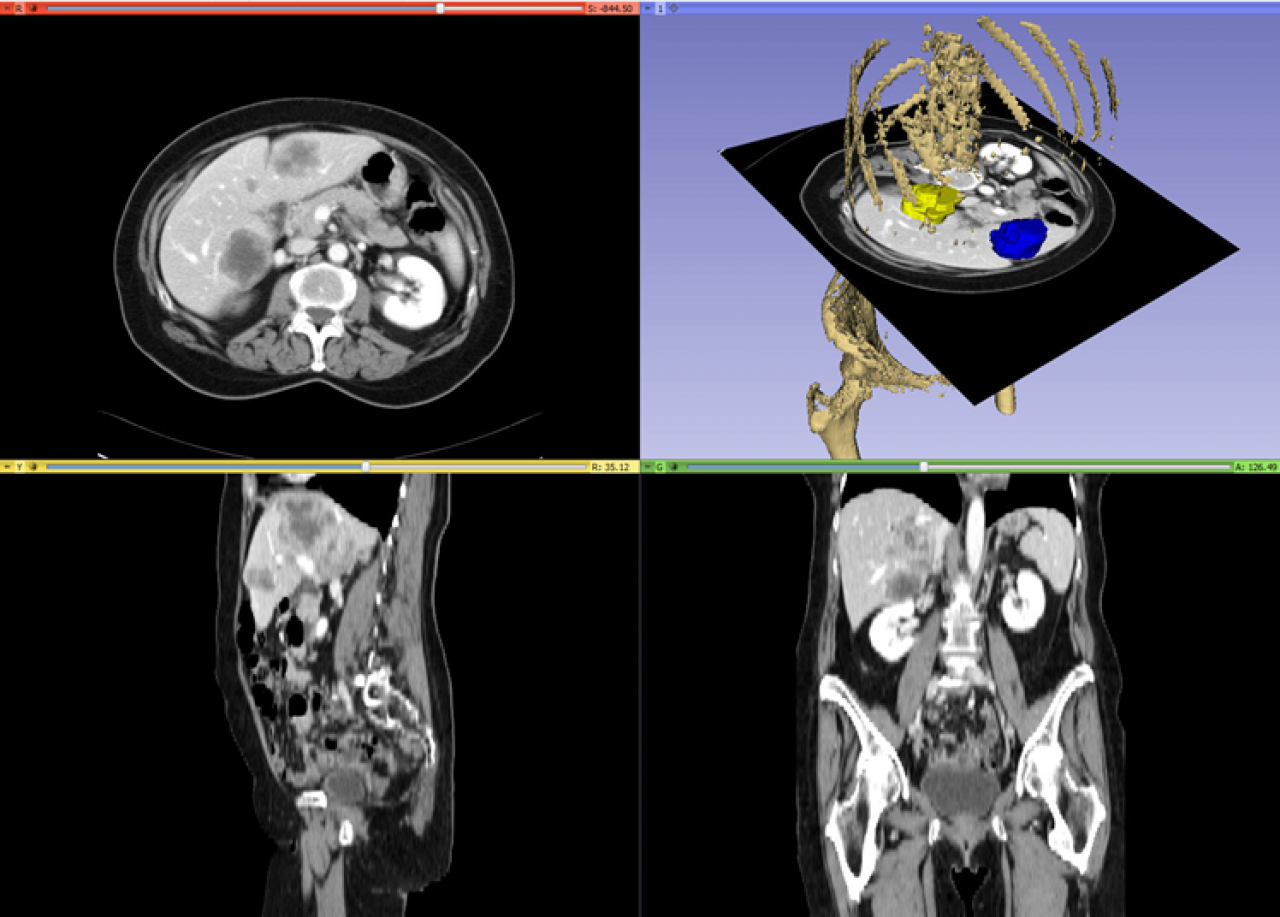

Spiral CT of Colon Cancer Imaging Features and Role in Management What Is Cancer Imaging Imaging techniques — methods of producing pictures of the body — have become an important element of early detection for many. Doctors use imaging tests to make pictures (images) of the inside of your body. Doctors use imaging tests to take pictures of the inside of your body. Mri (magnetic resonance imaging) helps doctors find cancer in the body and. What Is Cancer Imaging.